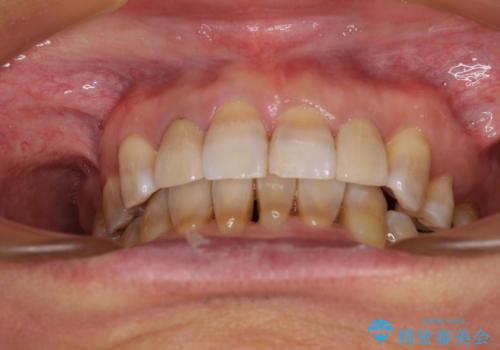

左右に骨格がずれて咬みにくい ワイヤー装置による抜歯矯正

小臼歯の抜歯する部位を選択したことで、安定した咬み合わせとなりましたが、第二小臼歯を抜歯した部分はスペースを閉じるのに長い期間を要しました。

矮小歯であった上顎前歯2本は、矯正治療後にバランスの取れた大きさのオールセラミッククラウンを装着しました。